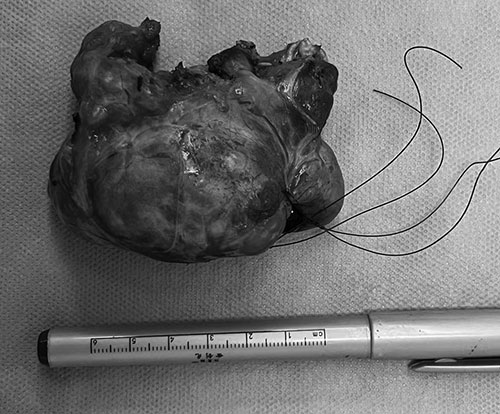

10月31日,在麻醉科于东男主任的密切配合下,在吴泽宇主任的指导下,黄毅捷主任带领手术团队为患者在全麻下行胸骨后甲状腺肿切除术。术中探查发现,甲状腺肿累及胸骨后方,至主动脉弓层面,手术难度大。在外科医生的精湛技术和团队的保驾护航下,仅1小时,便完整切除了一个9.5x5.5x5cm的巨大胸骨后甲状腺肿,术中出血极少,喉返神经和甲状旁腺均得到了完好保留。